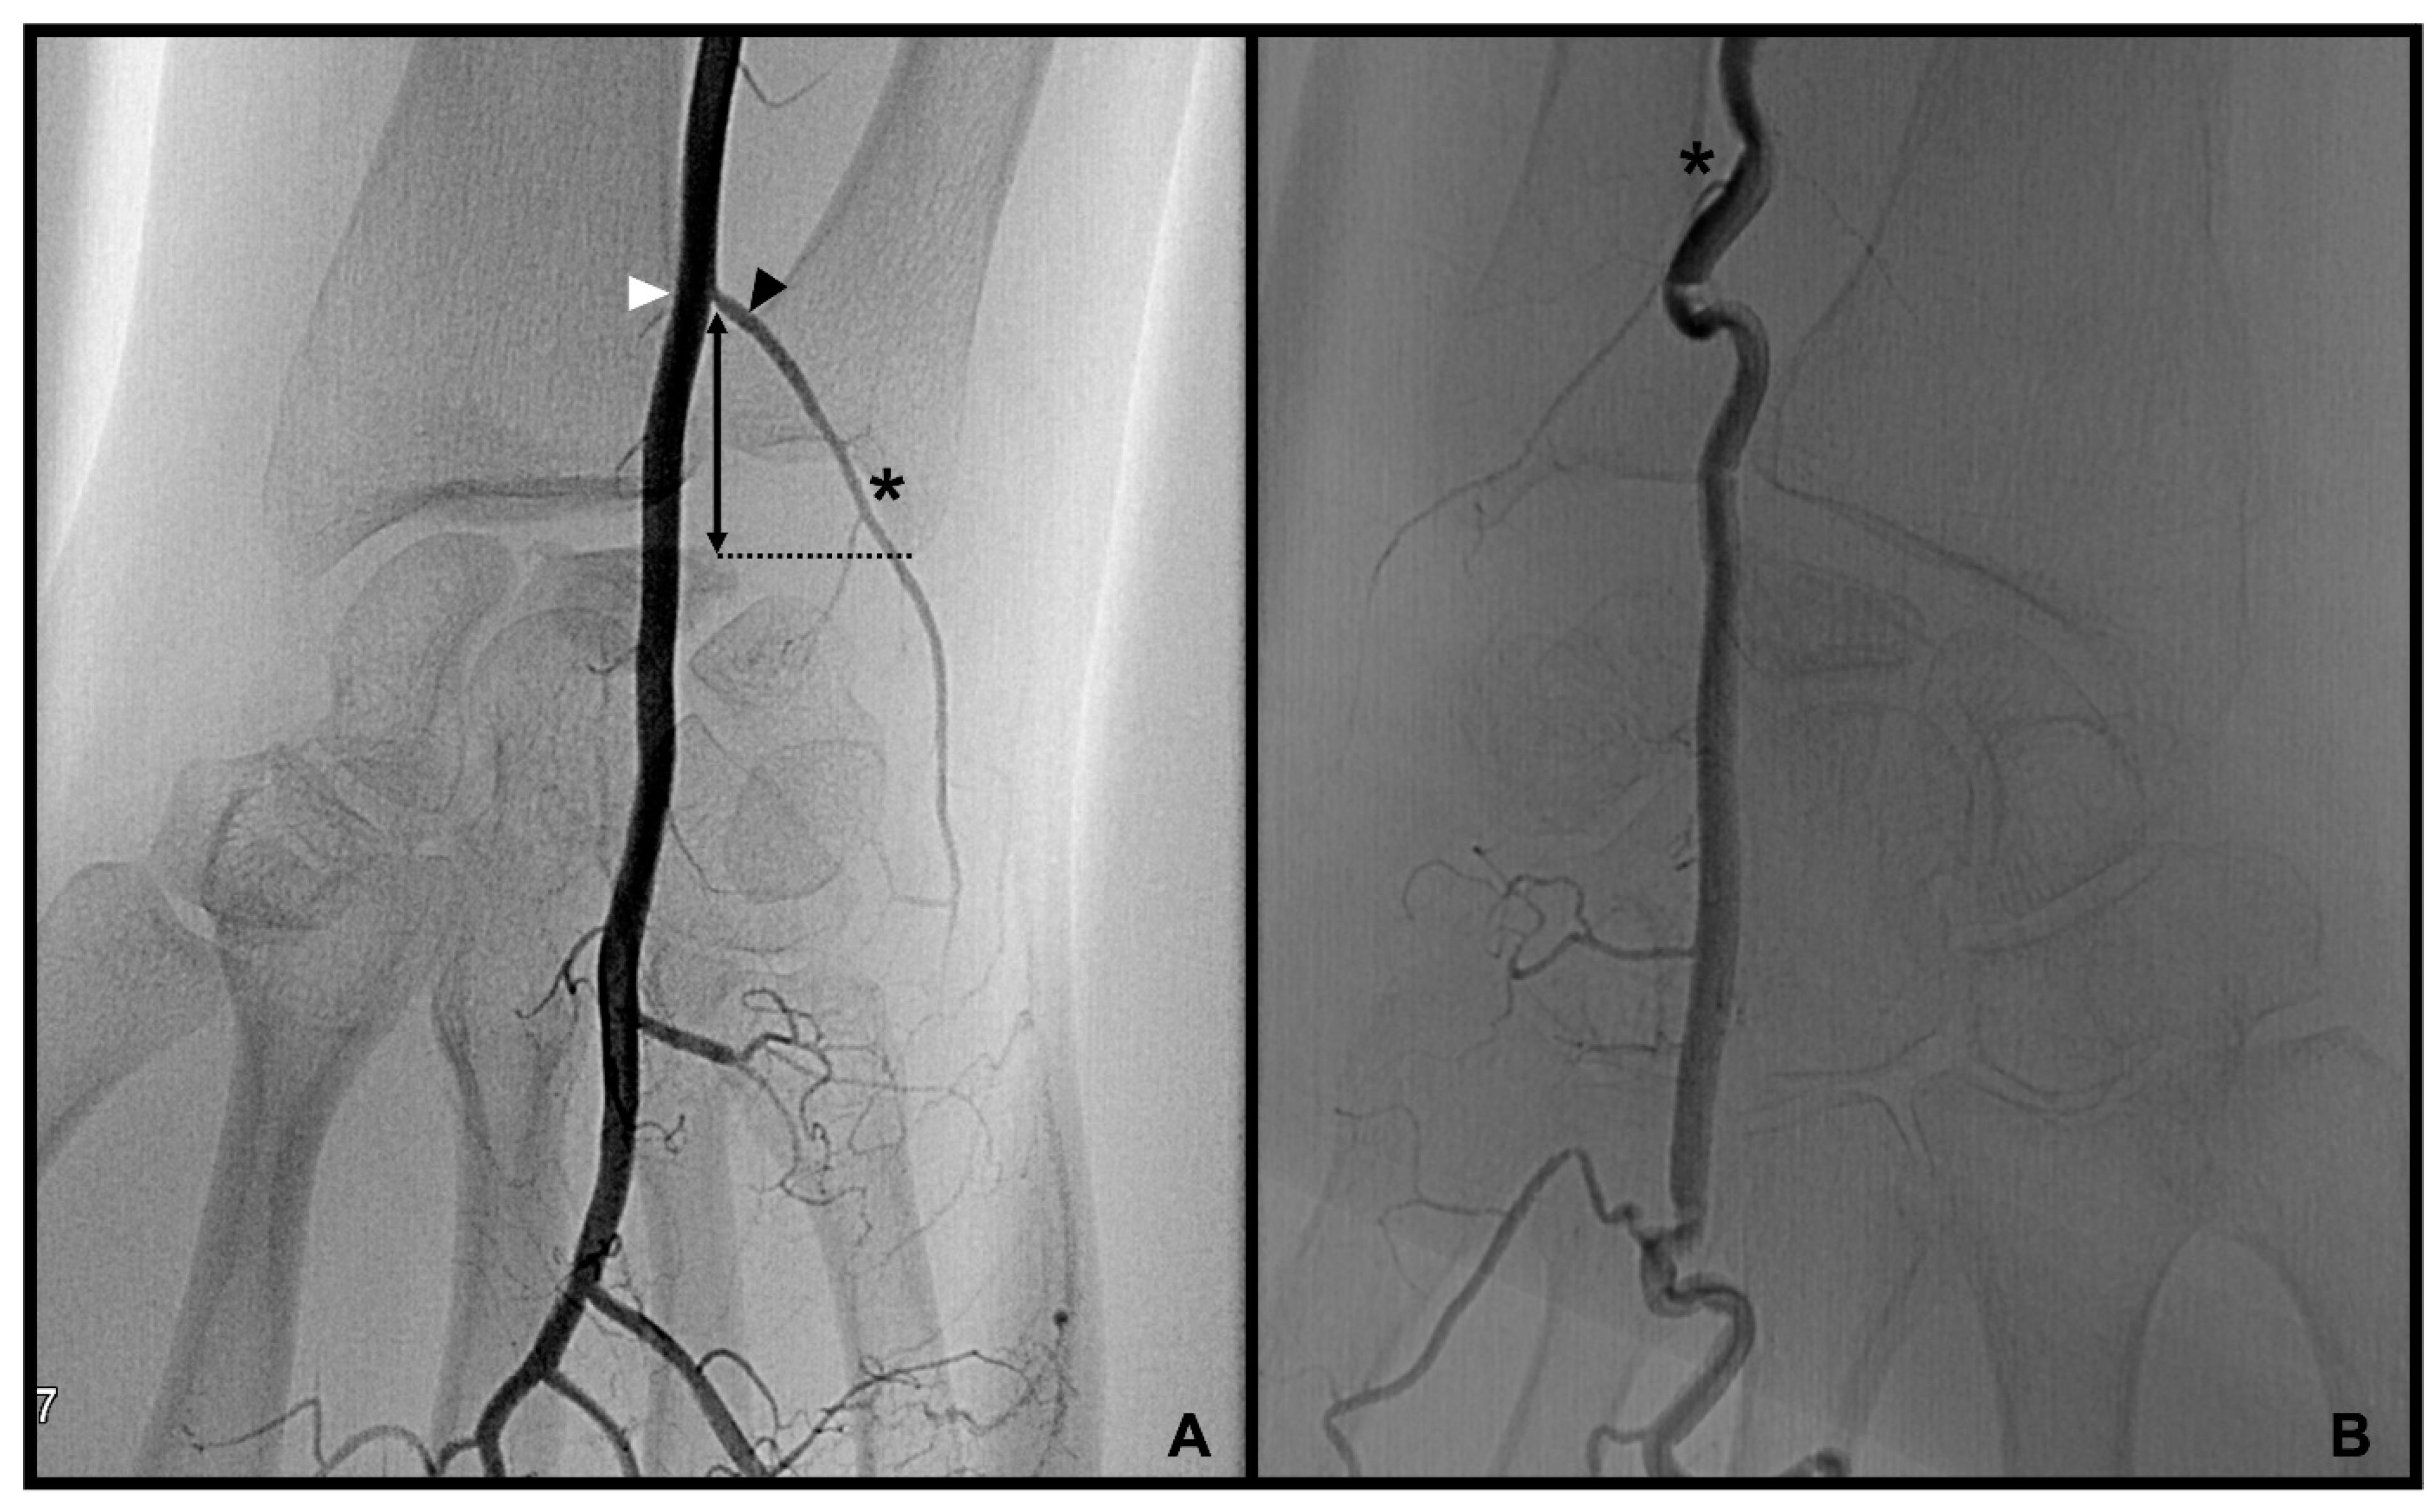

3.2. Dorsal Carpal Branch of the Ulnar Artery (DCBUA)

distance from the DCBUA to the styloid process of the ulnar (DCBUA = dorsal carpal branch of the ulnar artery).